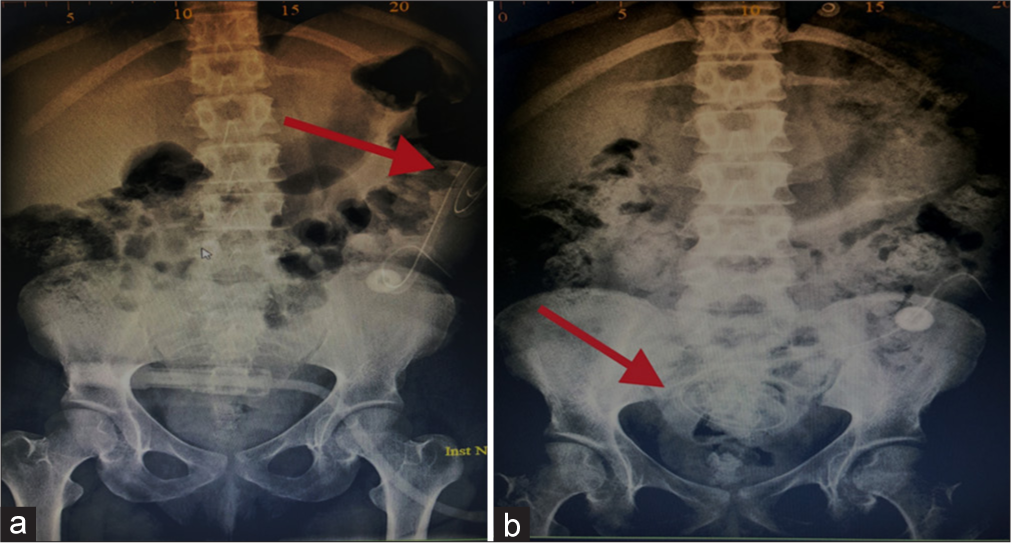

Similarly, patients presented with frequent alarms of low drain volume and poor UF due to catheter migration required hospitalization between 3 and 5 days for surgical correction of catheter position using a laparoscopic technique and evaluation of therapy after adjustment, as illustrated in Photo 1a and 1b.

- Compares two abdomen X-ray images pre and post catheter reposition for patient presented with continues alarm of low drain and low UF. It showed catheter migration and patient required surgical intervention for correction of PD Catheter position. (a) The red arrow in photo 1a shows that the PD catheter has migrated to the left upper quadrant of the abdomen and requires reposition. (b) The red arrow in photo 1b shows the PD catheter shadow in the pelvic region and it indicates that the catheter is back to the correct position after surgical intervention. UF: Ultrafiltration, PD: Peritoneal dialysis.